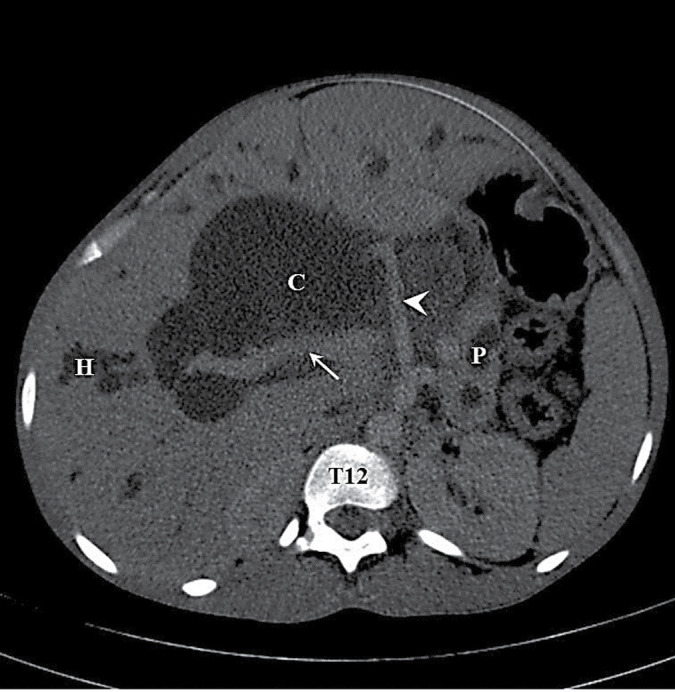

我们为您介绍一例 26 岁女性的病例,她出现了阻塞性黄疸和腹部肿胀。检查发现她患有巨大胆总管囊肿,并伴有梗阻性高胆红素血症。她接受了剖腹探查手术,引流并切除了胆总管囊肿,同时进行了 Roux-en-Y 肝空肠吻合术。随访 6 个月后,她的临床状况良好。

We present the case of a 26-year old woman who developed obstructive jaundice and massive abdominal swelling. Investigations revealed a huge choledochal cyst with obstructive pattern of hyperbilirubinaemia. She had exploratory laparotomy, drainage and excision of the choledochal cyst and Roux-en-Y hepaticojejunostomy. She has been followed up for 6 months in good clinical condition.